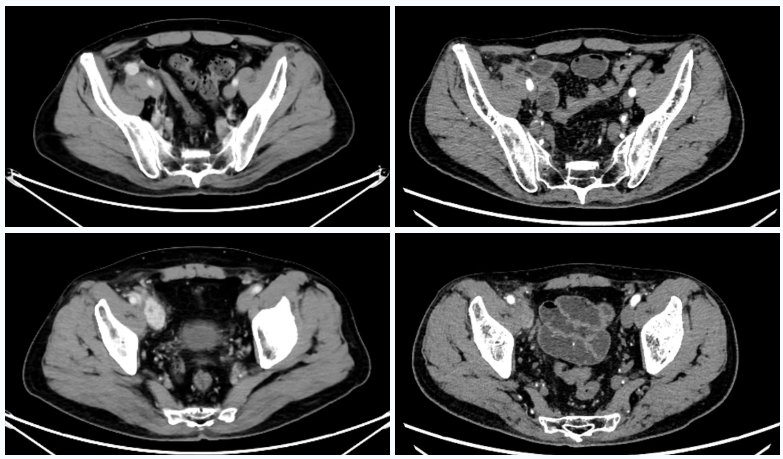

△2025年8月疗效评估时患者CT检查(右)较基线(左)对比

△2025年8月疗效评估时患者CT检查(上)及SPECT骨扫描(下)提示新发胸椎转移